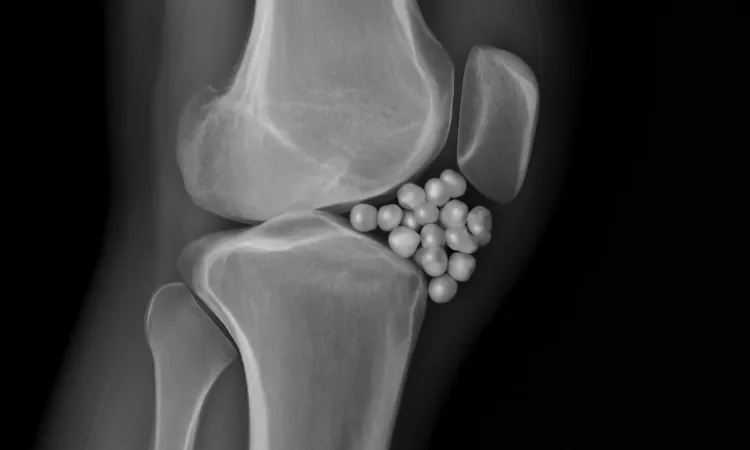

Хондроматоз коленного сустава представляет собой редкое заболевание, затрагивающее хрящевую ткань колена. Эта патология характеризуется образованием множества мелких хрящевых узелков, которые могут не только вызывать болезненные ощущения, но и существенно ограничивать подвижность сустава. Основная опасность заключается в прогрессирующем разрушении суставного хряща, что может привести к более серьезным последствиям и нарушениям функции ноги.

Ключевым методом диагностики является МРТ коленного сустава. Этот неинвазивный метод позволяет получить высококачественные изображения хрящевой ткани, связок и других структур сустава. Магнитно – резонансная томография помогает выявить наличие хрящевых узелков и оценить степень их влияния на окружающие ткани. В некоторых случаях могут быть назначены дополнительные методы диагностики, например, рентгенография или ультразвуковое исследование, для оценки состояния костной структуры и исключения других заболеваний.